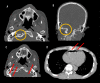

Case presentation: A 77-year-old man fell from a truck bed and suffered head and neck trauma. On hospital arrival, his consciousness was clear and his vital signs were stable. His chief complaint was pain in the back of his head and neck. Head CT showed traumatic subarachnoid hemorrhage in the right frontal area and basilar skull fracture of the occipital bone. Whole body CT showed pneumocephalus and air in the jugular vein and right ventricle. The patient was placed in the supine position in a state of absolute rest to prevent vascular air embolism and was treated conservatively. On hospital day 3, CT was reperformed, revealing disappearance of air in the right ventricle and decreased air in the veins of the head and neck. On hospital day 4, the air in the veins disappeared completely on CT. He did not experience vascular air embolism after increasing of his activity level (e.g., raising his head on hospital day 3 and standing and walking alone on day 5). He was discharged 34 days after admission without sequelae.